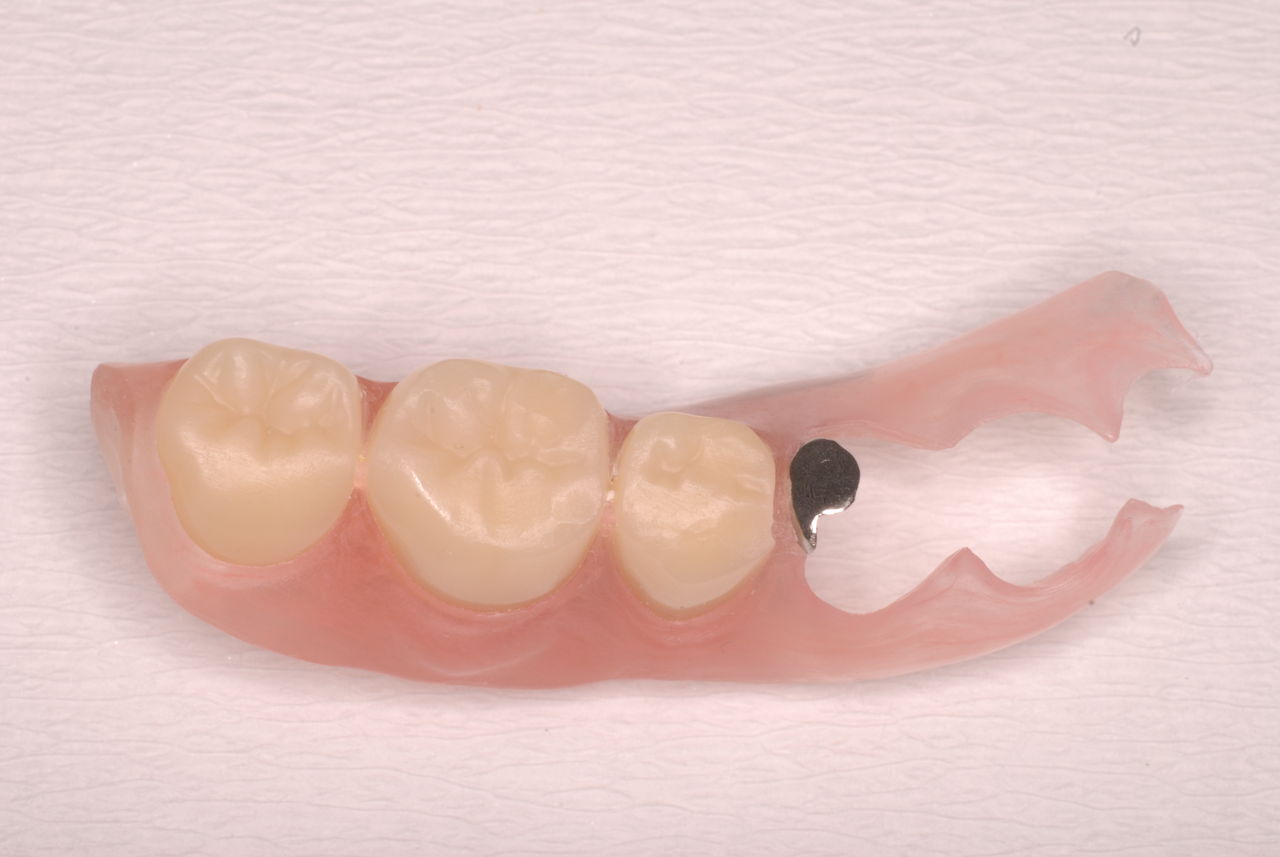

「川崎市の入れ歯なら新丸子西口歯科医院へ」

入れ歯のことなら入れ歯専門の新丸子西口歯科へ